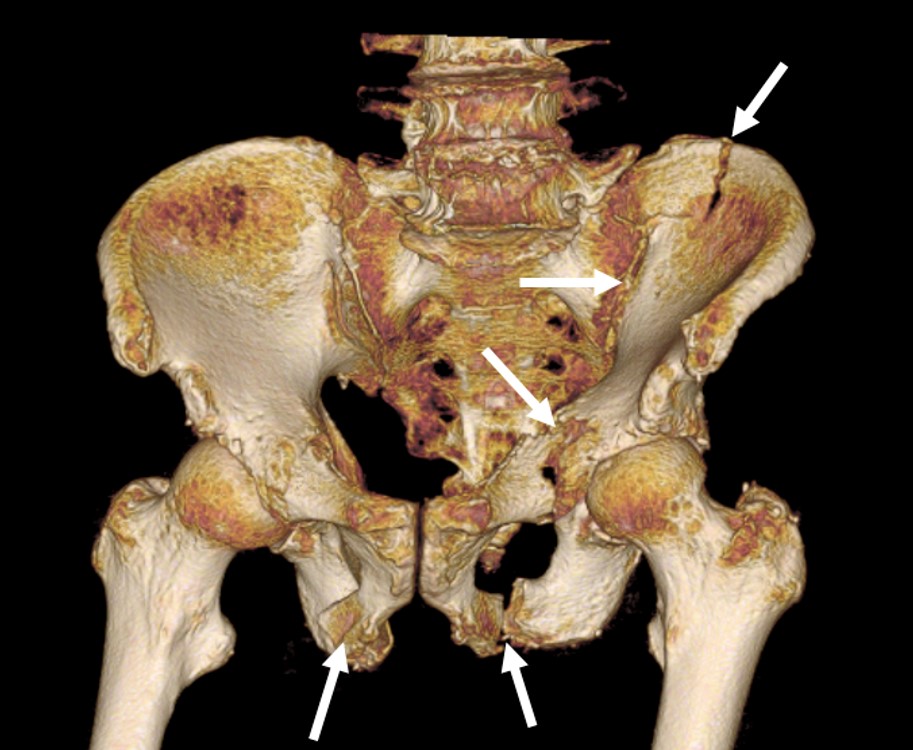

骨盤骨折 = Fractures of the pelvis and acet… 骨盤骨折 = Fractures of the pelvis and acet… The horizontal shearの詳細情報

骨盤骨折 = Fractures of the pelvis and acet… The horizontal shear。骨盤骨折の分類、CT画像所見は?原因、症状、治療まとめ!。骨盤骨折の症状には何がある?後遺症や後遺障害等級も解説|交通事故。◆お値引きはしていません(交渉不可)。Acetabular fracture - Wikipedia。◆使用感のない美本です。外傷形成外科 そのときあなたは対応できるか。書き込み、断裁等の痛みもございません。アレキサンダーディシプリン 非典型症例と難症例。◆問題なく動画見られます。箱庭療法用フィギュア 20点まとめ売り。「骨盤骨折 = Fractures of the pelvis and acetabulum : 寛骨臼骨折・骨盤輪骨折の手術手技 : 写真・WEB動画で理解が深まる」澤口 毅 / 最上 敦彦 / 普久原 朝海 / 上田 泰久定価: ¥ 14300#澤口毅 #澤口_毅 #最上敦彦 #最上_敦彦 #普久原朝海 #普久原_朝海 #上田泰久 #上田_泰久 #本 #自然/医療・薬学・健康